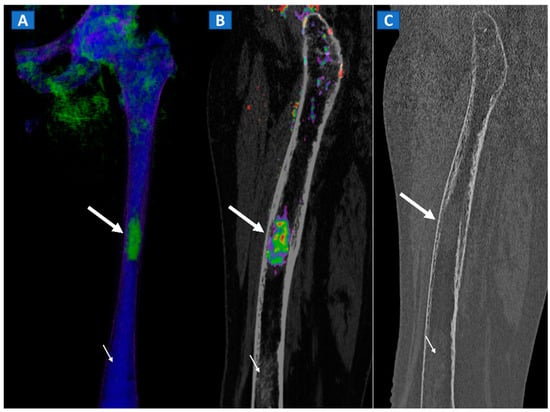

Figure 7.

A 42-year-old male long-distance runner with a bilateral tibial stress fracture. On the coronal STIR MRI images (A,E), a hypointense serpiginous subchondral line (arrows), surrounded by subtle BME involving the proximal tibia on the medial side, is depicted. On the DECT 3D maps (B,F) some BME is apparent around the fractures (arrows). On the corresponding DECT coronal 2D images (C,G), the presence of BME is confirmed (arrows), with a periphery to center gradient. The standard coronal reconstructed CT images (D,H) confirm the fracture lines (arrows). Note the absence of reactive sclerosis in the left knee (D) and the presence of sclerosis in the right one (H).

Stress fractures are caused by repetitive micro-traumatic injuries over time. Insufficiency fractures are a type of stress fracture commonly seen in osteoporotic women, resulting from normal stresses on abnormal bone. As for traumatic non-displaced fractures, DECT can identify stress fractures by depicting BME around the fracture line. High resolution morphological CT images can also be used to finely depict the course of a fracture line, and to distinguish fresh from old fractures depending on the presence of a reactive osteoblastic response (Figure 7).